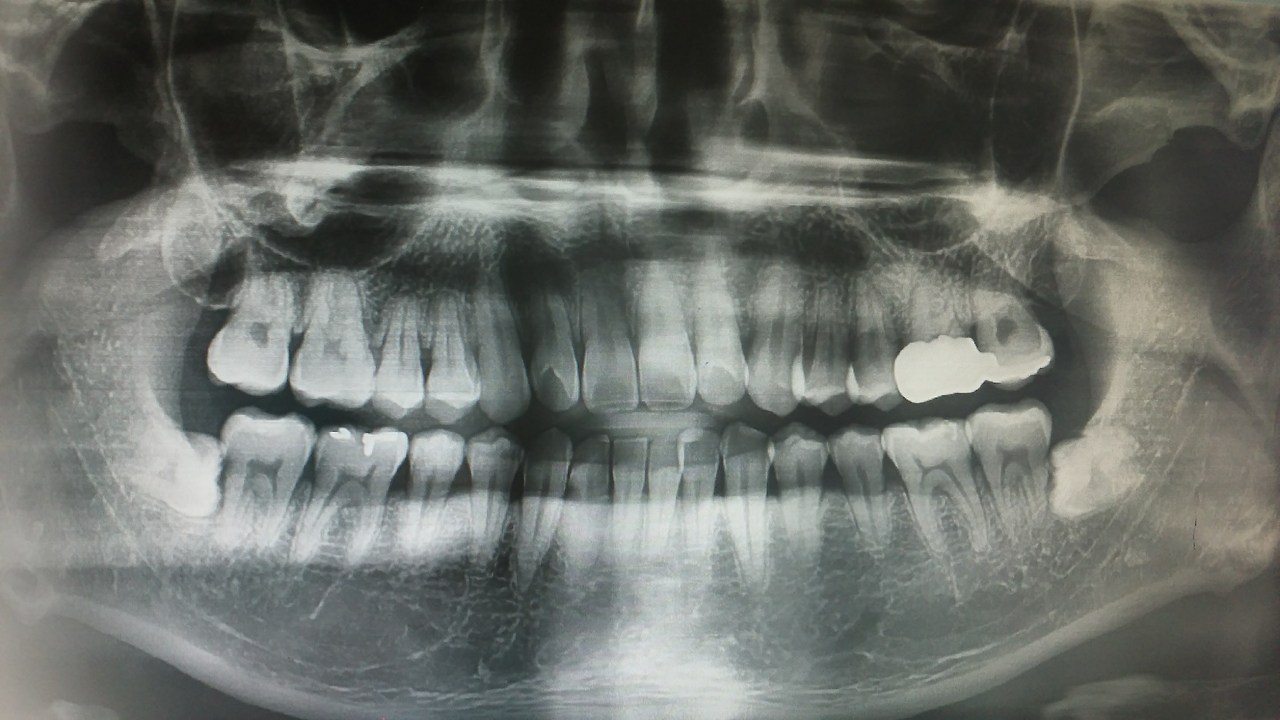

이번엔 좀 더 걱정스러운 치아손상에 대해 알아볼까요? 일단 아시다시피 치아는 뼈와 같은 단단한 조직입니다. 따라서 치료도 뼈 손상과 같습니다. 부러지거나 빠지면 제 위치에 자리하게 하고 고정을 해두는 것이죠. 따라서 치아가 빠지면 지체 없이 치아를 병원으로 가져와 제자리에 넣고 고정을 해줘야 합니다. 마침 젖니가 빠질 시기인 7-8세라면 다행이지만 영구치이거나 난지 얼마 안 된 젖니라면 얘기가 다르죠. 치아가 부러진 경우는 뒤에서 다시 설명하겠습니다.

빠진 치아는 어떻게 가져와야 할까요? 어디 떨어지지 않고 입에서만 빠진 경우 거나 거의 빠져서 덜렁거리는 경우라면 제자리에 밀어 넣고 살짝 입을 다물어 치과 응급치료가 가능한 대학병원을 찾는 것이 좋습니다. 어디서 치과 진료가 가능한지 모르신다면 119 상황실에 전화해 물어보셔도 됩니다. 만약 바닥에 떨어져 지저분한 이물질이 묻었다면 절대로 뿌리 부분을 잡거나 비비지 마시고 가까운 편의점 등에서 작은 팩우유를 하나 구입해 치아를 넣어 오시는 것이 좋습니다. 빨리 가져올수록 치아를 살릴 확률이 높아지므로 서둘러주세요.

치료는 어떻게 하는 걸까요? 치과에서는 스플린트라는 기구를 이용해 빠진 치아를 고정하게 됩니다. 고정해 둔다고 다 살아날 수 있다면 참 좋겠지만, 그렇진 않겠죠? 한 번 빠진 치아의 생착률은 25%가량 된다고 알려져 있습니다. 빠진 치아를 얼마나 빠르게 뿌리 부분이 손상되지 않도록 가져와 고정하냐에 따라 생착률, 그 치아를 살려 사용할 수 있을지가 결정되죠. 그래서 빠른 응급처치가 중요합니다. 안타깝게도 치아를 가져오지 않거나 뿌리 부분을 다 손상시킨 채 가져오는 경우는 도움을 드리기 어렵습니다.

이도 저도 안되면 결국 마지막 단계인 임플란트를 시행하게 됩니다. 자라면서 구강 구조와 치열이 변하는 소아 청소년에게는 임플란트를 시행할 수 없어 성장을 완료한 뒤 임플란트 치료를 하게 됩니다. 임플란트는 꽤 대수술입니다. 먼저 잇몸을 절개해 치아가 빠진 부분에 뿌리 역할을 하게 될 나사를 심습니다. 이후 턱뼈와 임플란트 뿌리가 충분히 붙은 뒤에는 임플란트 머리 부분을 마저 끼워주면서 완성합니다. 비용도 비용이지만 수술 전후 합병증도 크고 사용기간도 제한이 있어 임플란트까지 하게 되는 일은 가능한 막아야 합니다.